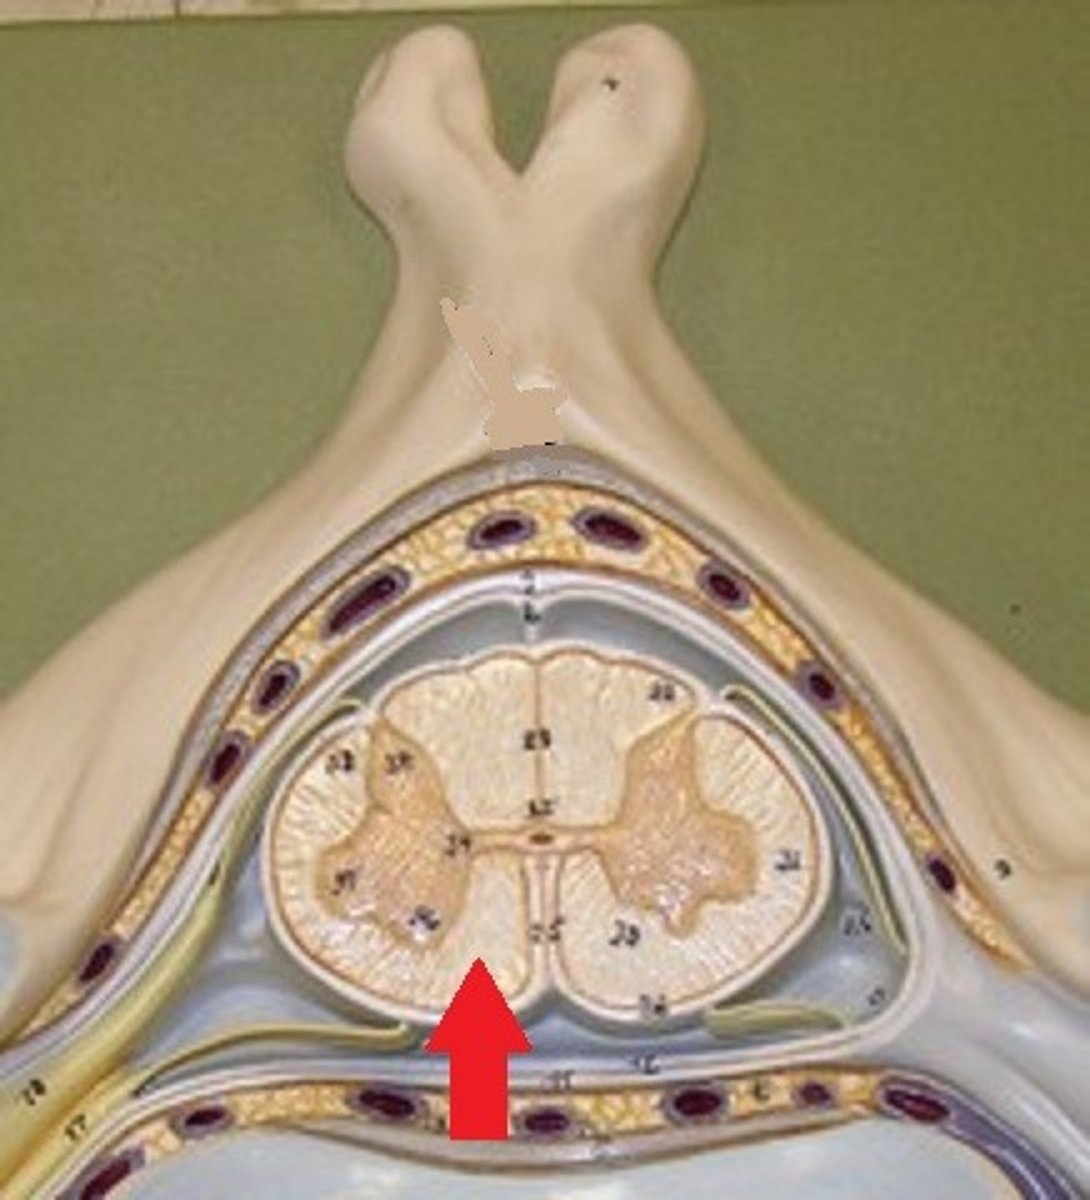

anterior white column

Information descends from the brain (Brings info back to the spinal cord)

motor commands

anterior median fissure

spinal meninges

3 specialized membranes surrounding spinal cord and brain

Stability, shock absorption, carry blood supply (oxygen and nutrients)

3 spinal meninges (Superficial to deep)

dura mater, arachnoid mater, pia mater

Dura mater

tough outer layer of the meninges

arachnoid mater

Made of simple squamous epithelium

Pia mater

thin, delicate inner membrane of the meninges

subarachnoid space

between arachnoid mater and pia mater

filled with cerebrospinal fluid

shock absorber; diffusion of gases, nutrients, etc.

blood vessels for spinal cord

epidural space

space between dura mater and vertebrae

denticulate ligaments

pia mater, through the arachnoid mater, to dura mater

Prevents lateral movement